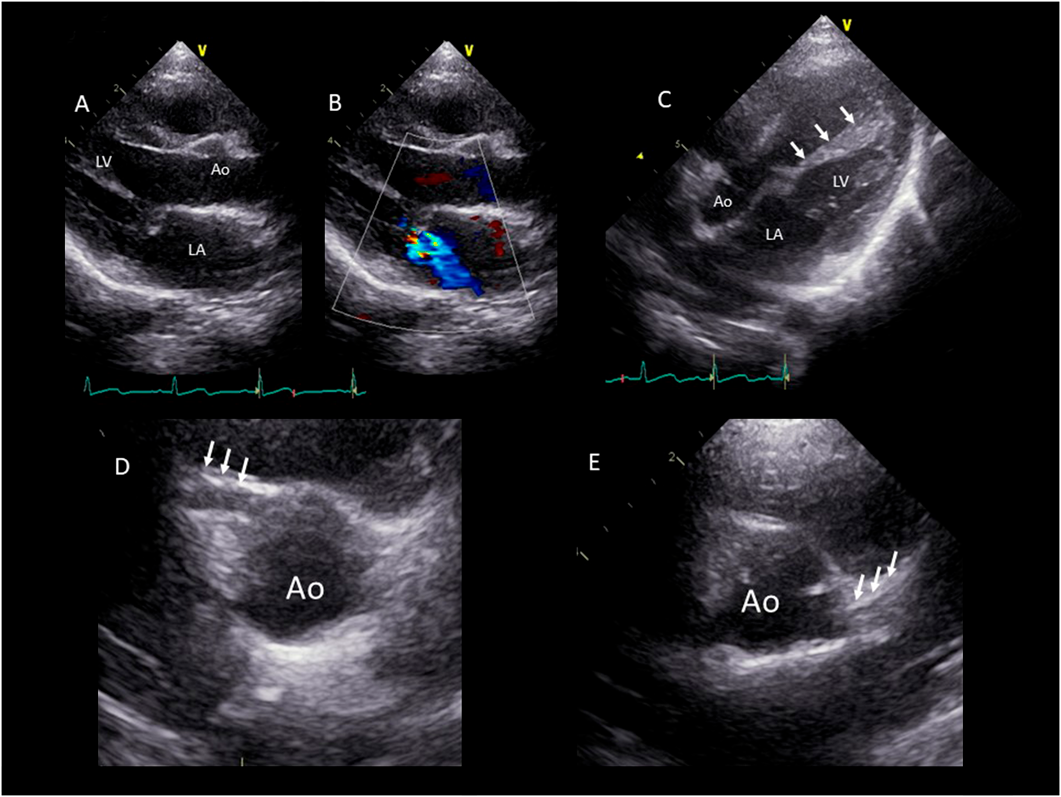

Chest radiograph showed a cardiothoracic ratio of 42%, and a 12-lead electrocardiogram at rest was normal with no ST changes (Fig. 1). Blood tests showed no abnormal findings with a human brain natriuretic peptide (BNP) level of 13.0 pg/mL. Echocardiography findings are shown in Fig. 2. The left ventricular end diastolic diameter was 30.1 mm (84.3% of our normal value), end systole diameter was 19.5 mm with ejection fraction of 70%, and mitral ring annulus diameter 20.9 mm (94.6% of our hospital normal value). The degree of mitral valve regurgitation was moderate according to the Color Doppler method. However, the left atrium/aortic ratio was 1.17, and there was no enlargement of the left atrium.

Fig. 2 Echocardiography findings

(A) Long-axis view of the left ventricle. The cause of mitral regurgitation was tethering rather than prolapse. (B) The degree of mitral valve regurgitation was moderate according to the Color Doppler method. (C) Five-chamber view of the left ventricle. The high echogenicity of the left ventricular papillary muscle is visualized. (D) The RCA has an enlarged starting point of 3 mm (Z score: 2.7) (arrow). (E) The left coronary artery is thin (arrow) with an unidentifiable origin. Ao, aorta; LA, left atrium; LV, left ventricle.

Due to the high echogenicity of the left ventricular papillary muscle, we suspected abnormalities in the left coronary artery. The right coronary artery was enlarged to 3 mm (2.7 in Z-score), whereas the left coronary artery was thin with an unidentifiable origin. Therefore, we performed myocardial scintigraphy using techenetium-99m (99mTc)-tetrofosmin perfusion agents with adenosine loading. Immediately after the adenosine loading, she complained of chest pain with negative conversion of T wave on an electrocardiogram. On adenosine loading, the accumulation of 99mTc-tetrofosmin was slightly decreased from the anterior wall to the apex, but at rest, the accumulation at the same site was further reduced (Fig. 3).